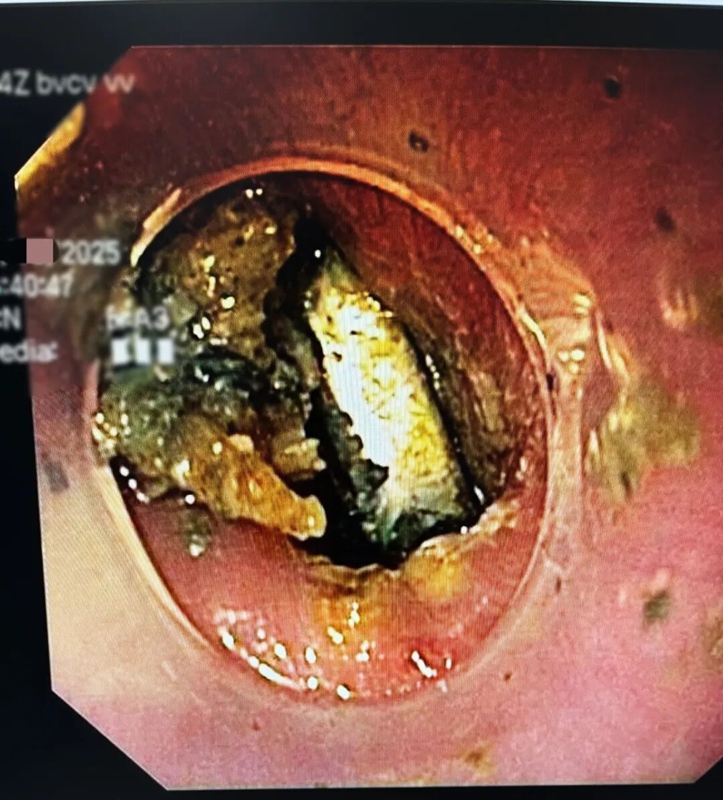

術(shù)前檢查剛一完成,醫(yī)師便迅速開展胃鏡手術(shù),此時畫面讓人揪心:紐扣電池已牢牢嵌頓在食管處,周圍黏膜不僅明顯水腫,還出現(xiàn)了黑焦樣的腐蝕痕跡。

這枚“滾刀肉”般的紐扣電池取出難度極大,醫(yī)師憑借精準操作,終于用異物鉗將其成功取出。若再晚一步,可能導(dǎo)致食管穿孔、大出血,甚至危及生命。